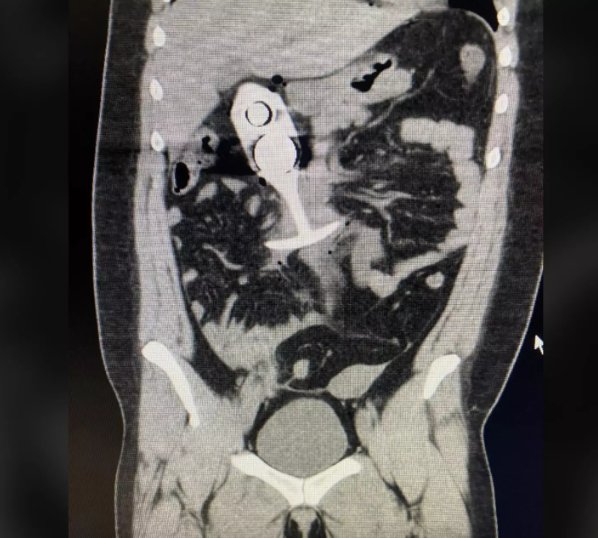

Prieš tyrimą pacientų klausiama, ar jų kūne nėra metalinių implantų ar kitų objektų. Nelaiminga pacientė, manydama, kad jos naudojamas sekso žaislas yra pagamintas tik iš silikono, jo nenurodė. Deja, žaislo viduje buvo metalinė šerdis, kurią galingas magnetas akimirksniu pritraukė.

Dėl to moteris patyrė stiprų skausmą, nes žaislas staiga pajudėjo jos kūne. Teigiama, kad jis „garso greičiu“ šovė į krūtinės ląstą, nors ekspertai šį teiginį laiko perdėtu. Lankasterio universiteto profesorius Adamas Tayloras aiškina, kad feromagnetiniai objektai MRT lauke gali pasiekti didelį greitį – iki 40 mylių (64,37 kilometro) per valandą, tačiau garso greičio jie nepasiektų.

Incidento nuotrauka buvo paviešinta socialiniuose tinkluose, sukeldama didžiulį žmonių siaubą ir diskusijas apie MRT tyrimų saugumą. Moteriai iškart po tyrimo buvo suteikta medicininė pagalba, ji išvežta į ligoninę, tačiau jos dabartinė būklė nėra žinoma.